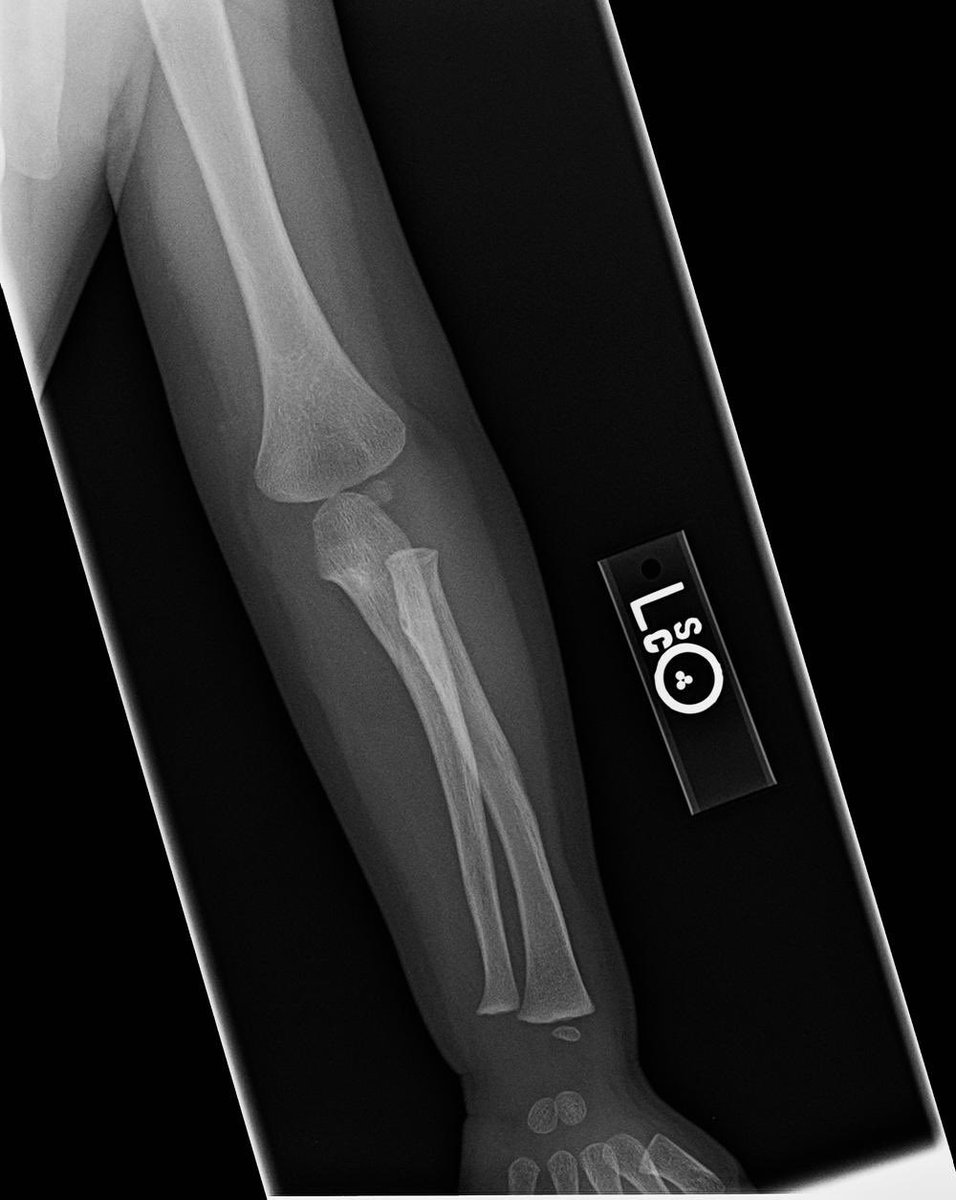

- التأكد من عدم حدوث إصابات المرفق الاخرى الشائعة الحدوث ككسور أعلى الساعد أو أسفل العضد.

-قد يستلزم الأمر إجراء فحص بالأشعة.